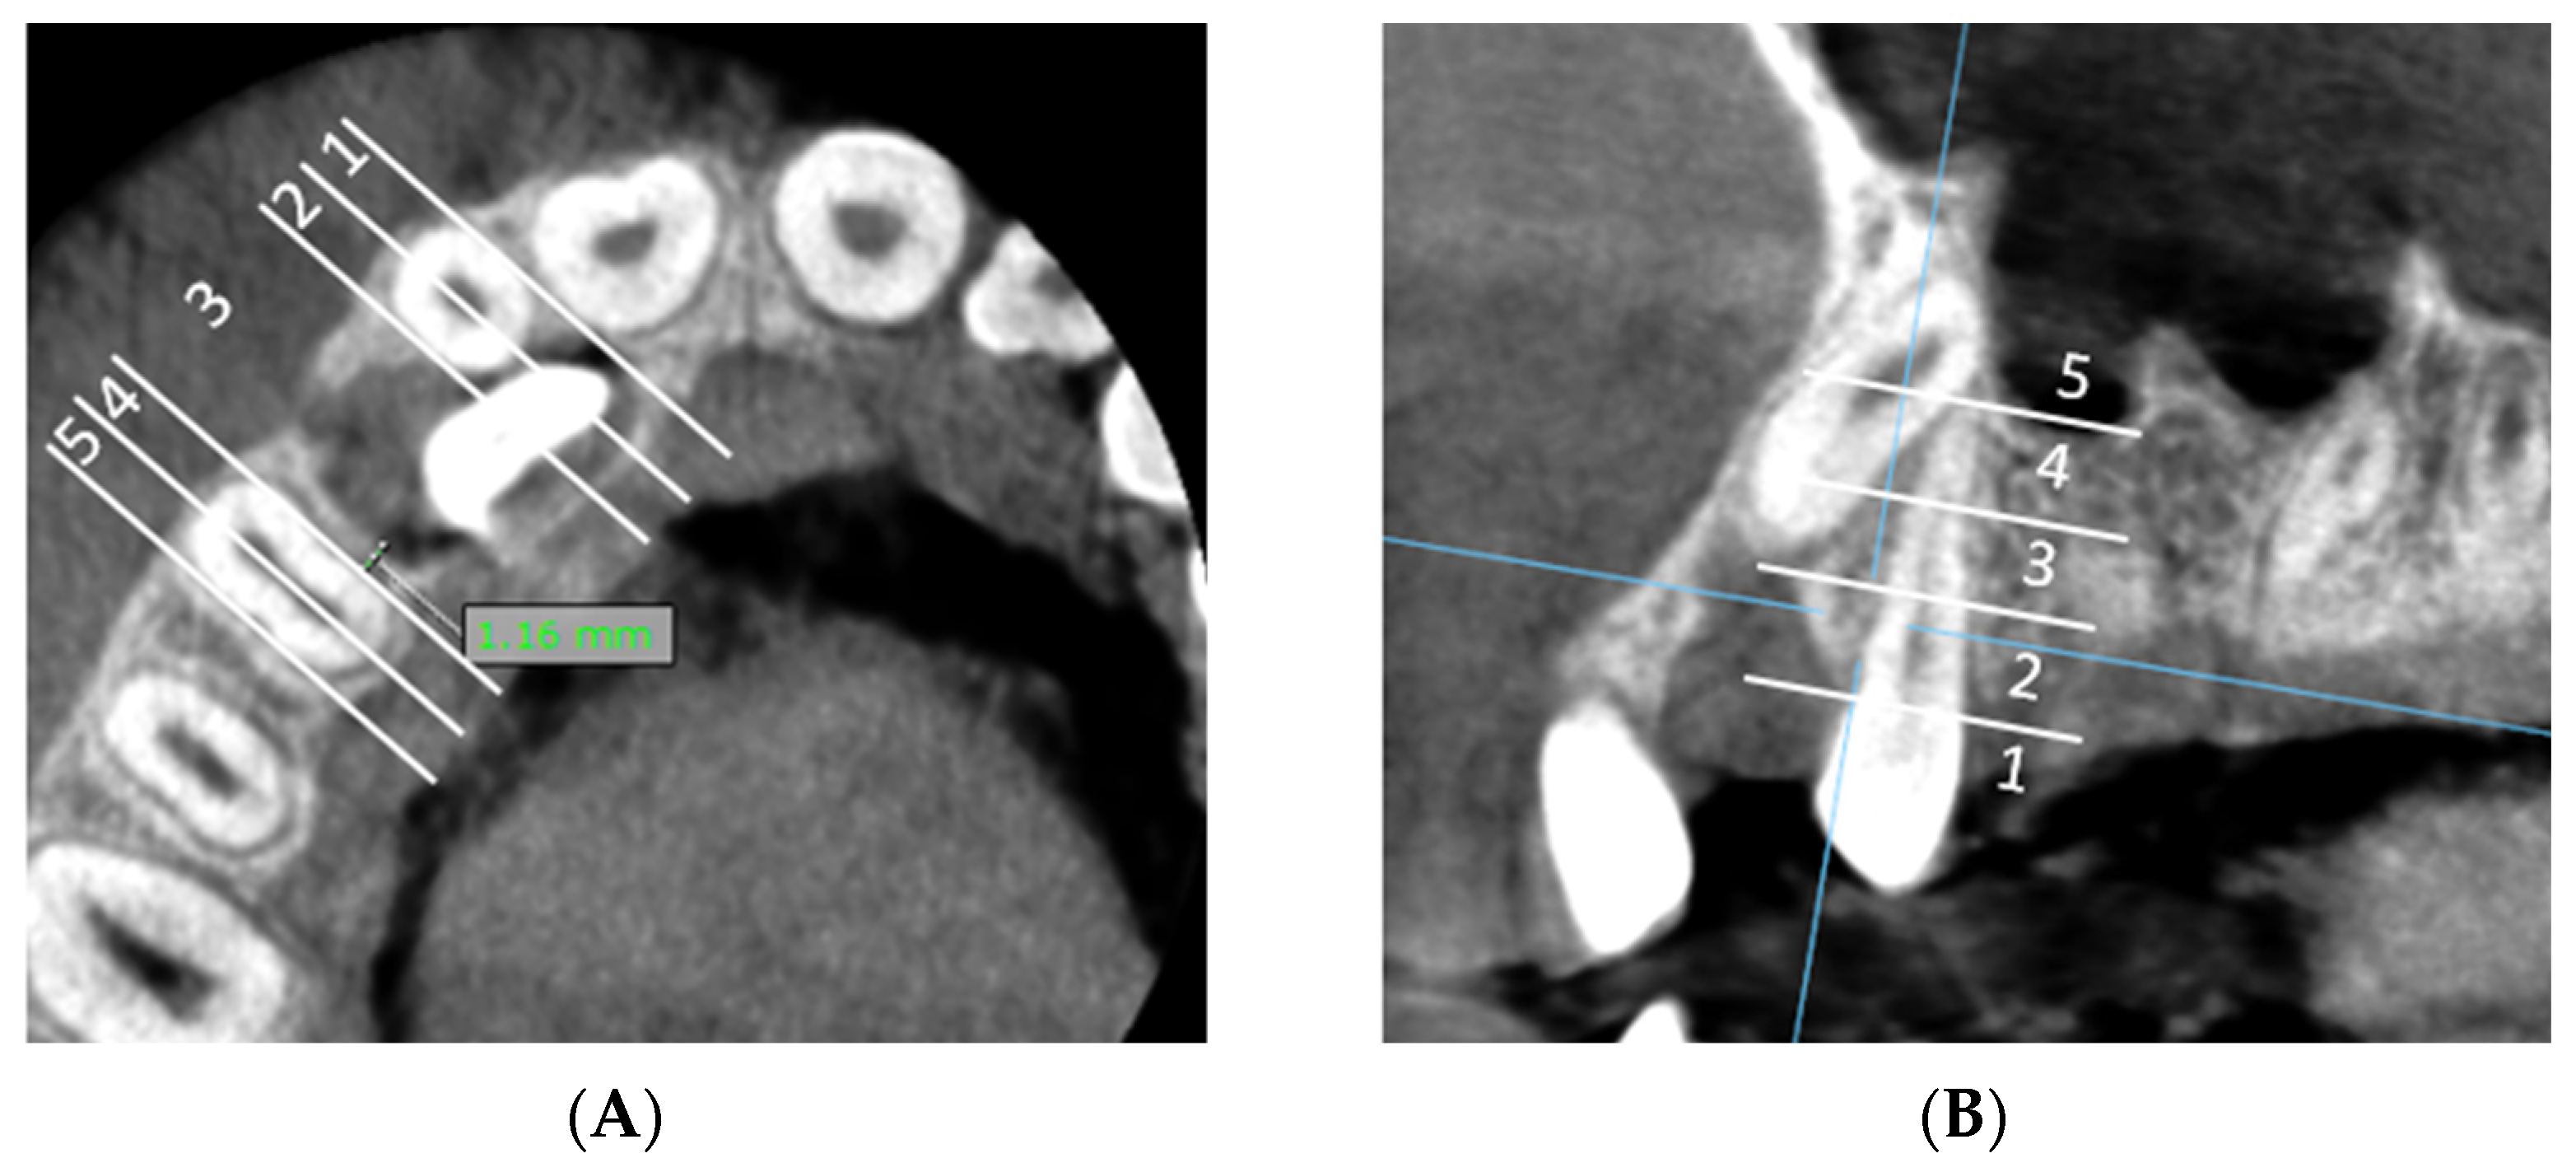

A: Measurement of the shortest distance between impacted canine and lateral incisor and classification of the shortest distance in horizontal zone of impaction (Figure 2A).

Figure 2. CBCT evaluation: (A) horizontal zone of impaction of the maxillary canine in relation to the lateral incisor (axial CBCT slices): the shortest distance between the lateral incisor and the impacted canine is located in horizontal impaction zone 2. (B) Vertical zone of impaction of the maxillary canine in relation to the lateral incisor (sagittal slices): the shortest distance between the lateral incisor and the impacted canine and is located in vertical impaction zone 3. (C) Horizontal zone of impaction of the maxillary canine in relation to the first premolar (axial CBCT slices): the shortest distance between first premolar and the impacted canine is located in horizontal impaction zone 3. (D) Vertical zone of impaction of the maxillary canine in relation to the first premolar (sagittal slices): the shortest distance between the first premolar and the impacted canine is located in vertical impaction zone 5.

B: Classification of the shortest distance within the vertical zone of impaction relative to the lateral incisor (Figure 2B).

C: Measurement of the shortest distance between impacted canine and first premolar and classification of the shortest distance in horizontal zone of impaction (Figure 2C).

D: Classification of the shortest distance within the vertical zone of impaction relative to the first premolar (Figure 2D).

We divided the horizontal and vertical dimensions into five zones (1–5 zones) (Figure 2).

Horizontal zone of impaction (Figure 2A,C):

• Horizontal zone 1: Mesial half of the maxillary lateral incisor.

• Horizontal zone 2: Distal half of the maxillary lateral incisor.

• Horizontal zone 3: The area between distal point of the lateral incisor and mesial point of the first premolar.

• Horizontal zone 4: Mesial half of the maxillary first premolar.

• Horizontal zone 5: Distal half of the maxillary first premolar.

Vertical zone of impaction (Figure 2B,D):

• Vertical zone 1: The area inferior to the cementoenamel junction of the lateral incisor/first premolar.

• Vertical zone 2: The lower third of the vertical length (measured from the cementoenamel junction to the apex) of lateral incisor/first premolar.

• Vertical zone 3: The middle third of the vertical length (measured from the cementoenamel junction to apex) of lateral incisor/first premolar.

• Vertical zone 4: The upper third of the vertical length (measured from the cementoenamel junction to the apex) of lateral incisor/first premolar.

• Vertical zone 5: The area superior to the apex of the lateral incisor/first premolar.

Figure 3. (A) The minimal distance between the dental follicle of the impacted canine and the adjacent upper lateral incisor is 0 mm, indicating direct contact between the distal surface of the lateral incisor’s root and the dental follicle, and is classified in horizontal zone 2. The minimal distance between the dental follicle of the impacted canine and the adjacent first premolar is 1.16 mm and is classified in horizontal zone 3. (B) The shortest distance between the dental follicle of the impacted canine and first premolar is located in vertical impaction zone 2.